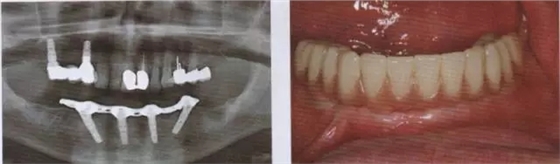

圖12 戴入即刻l臨時修復(fù)體。

圖13 在取下上部結(jié)構(gòu)后可以看到完全無刺激反應(yīng)的軟組織

圖14 在下頜種植手術(shù)一年后可以看到種植體周圍骨水平穩(wěn)定且拔牙窩形成進(jìn)一步的骨再生

圖15 在帶入終修復(fù)體后檢查,種植體完全無炎癥